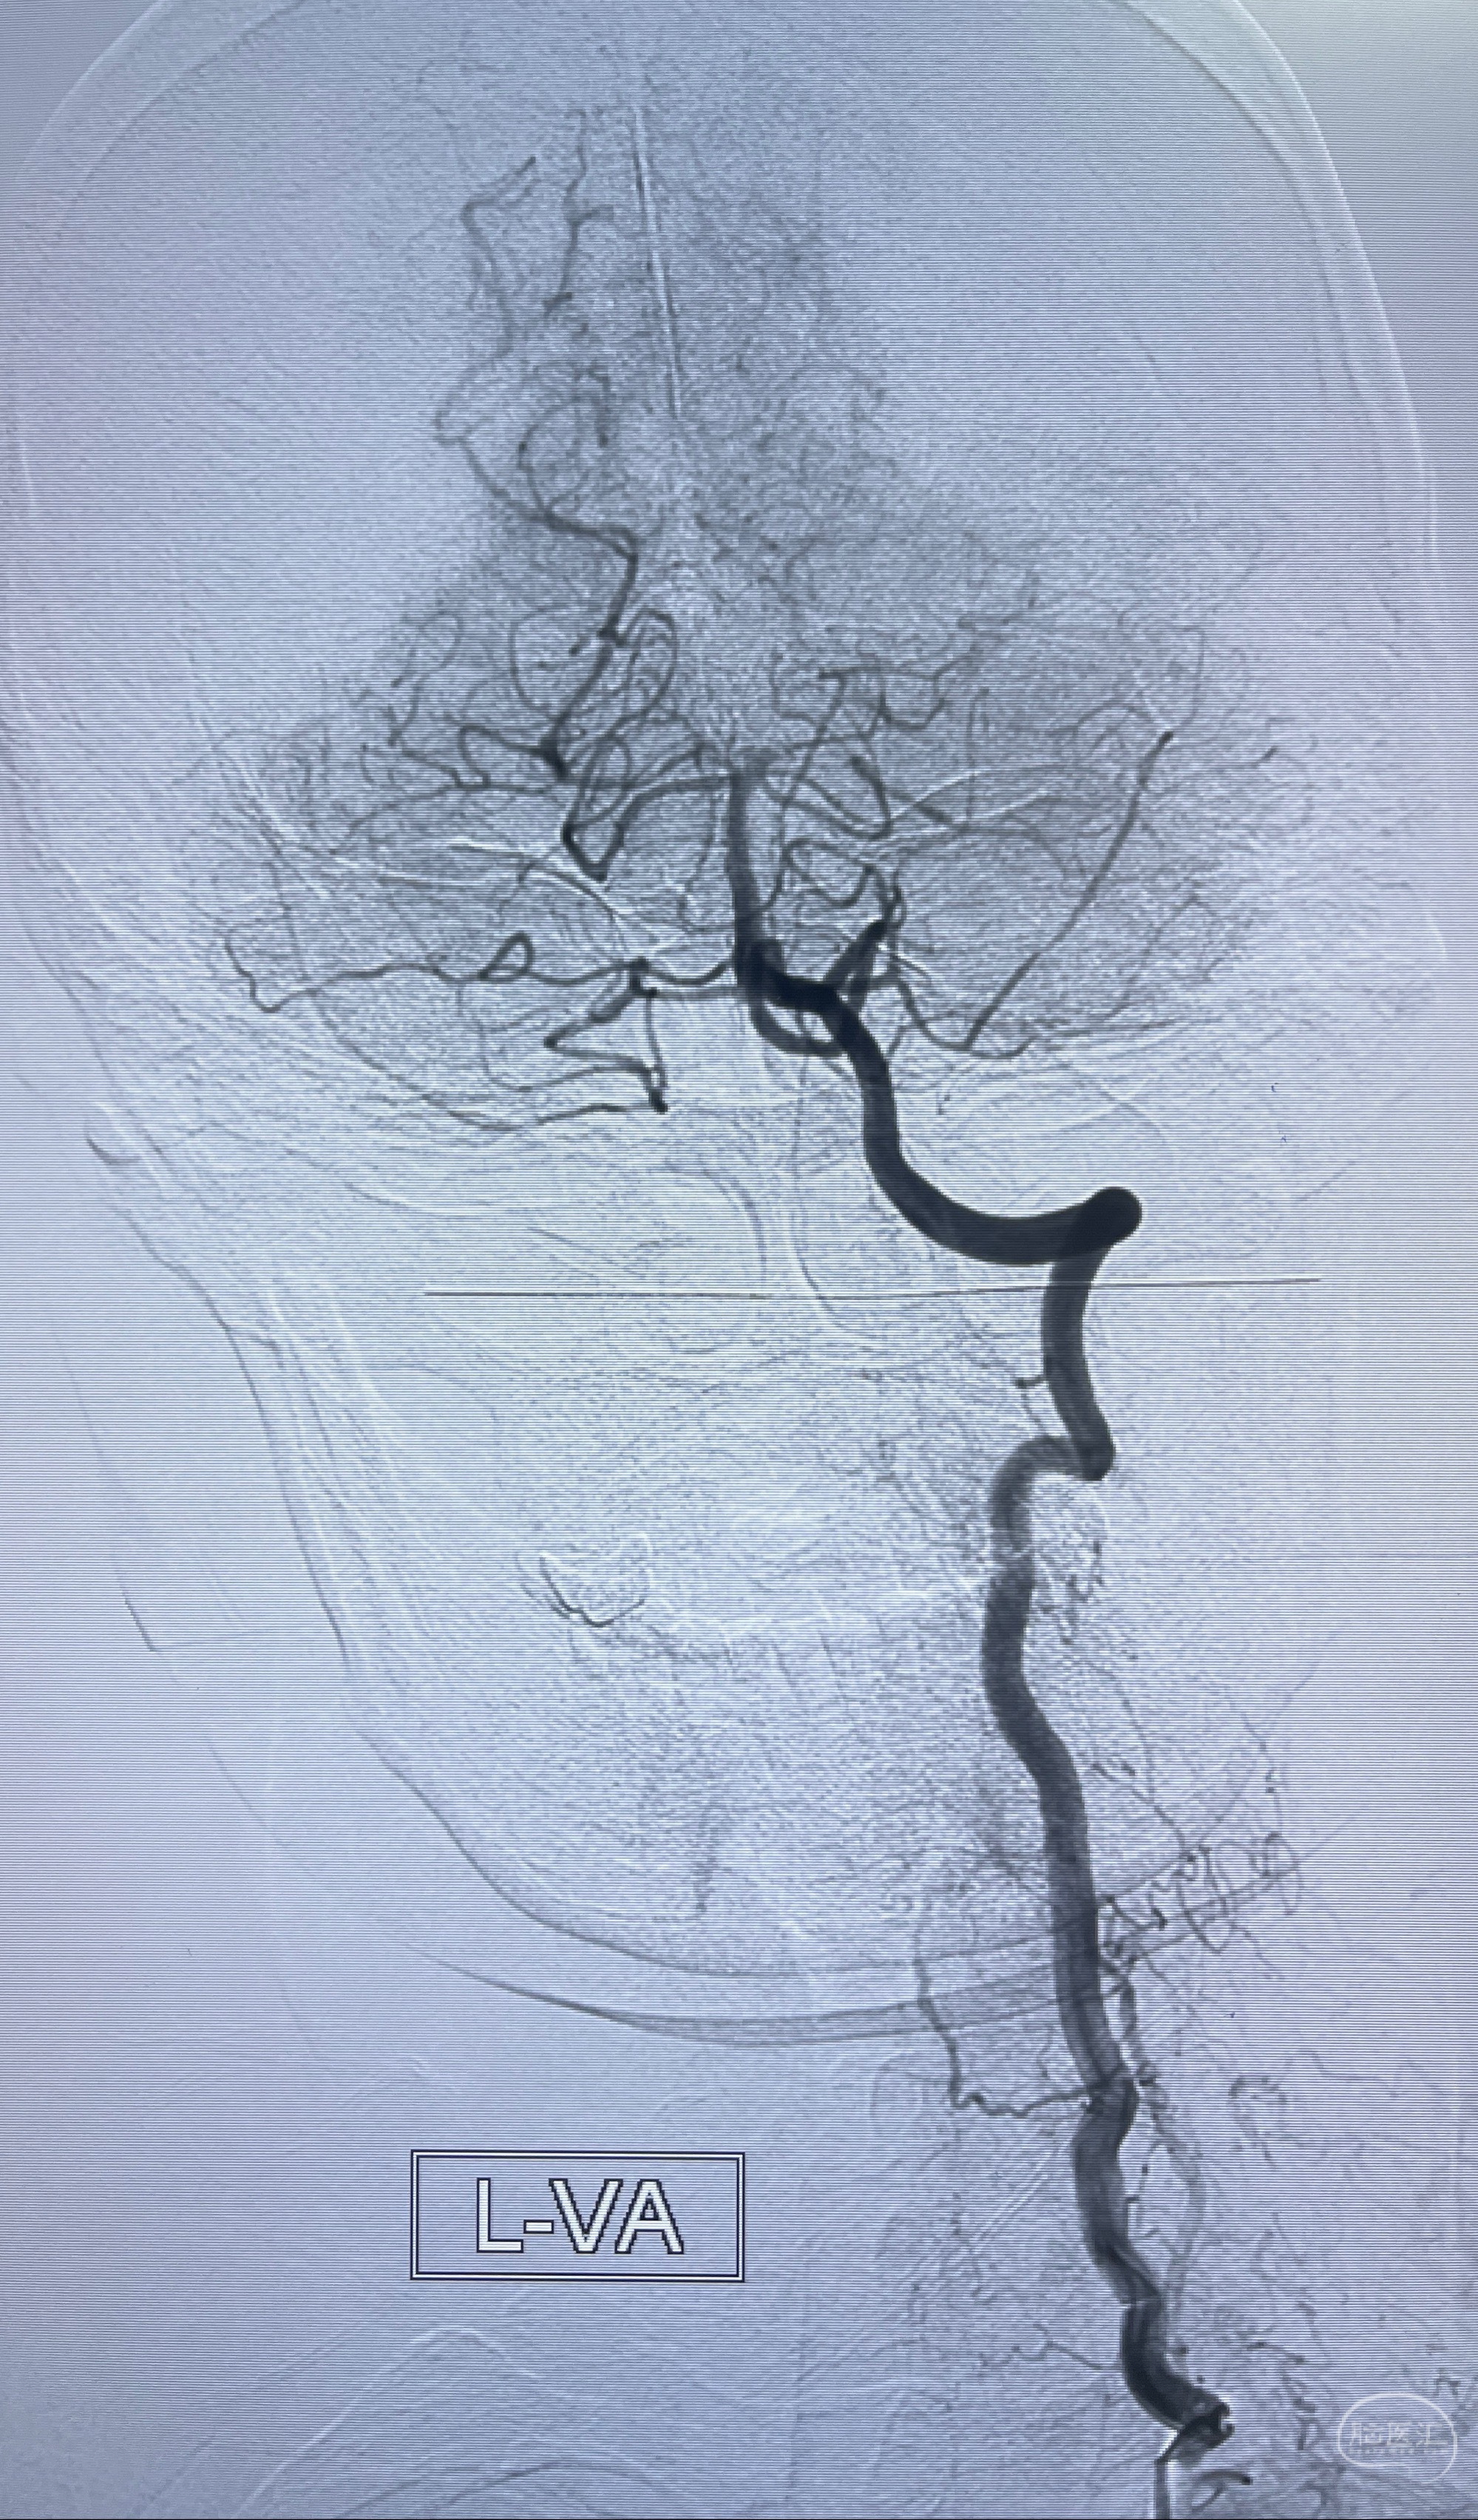

检查;2023-7-18 抚州市第一人民医院 头颈部CTA:左侧大脑前动脉A2段动脉瘤,左侧颈内动脉C4段轻度狭窄,右侧颈内动脉C6段中度狭窄

1.左侧大脑前动脉远侧段(A2-A5)动脉瘤

2023-08-23DSA:左侧前交通动脉瘤,左侧A3/4交界处多发动脉瘤